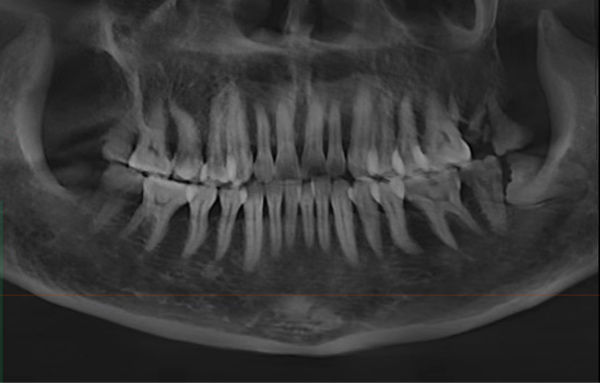

“最開始她以為是之前治療過的那顆牙(右上第一前磨牙)又出問題了,但我們仔細檢查后發現,真正讓她痛得睡不著的是另一顆快被蛀空的大牙(右上頜第二磨牙)。”黃醫生回憶道,“那顆牙表面已經蛀得不成樣子,一碰冷水就疼得直抽氣,輕輕敲擊也疼得厲害。當時她特別擔心要反復治療,我們就商量著把兩顆鄰近的牙一起做了根管治療,也避免她來回奔波。”